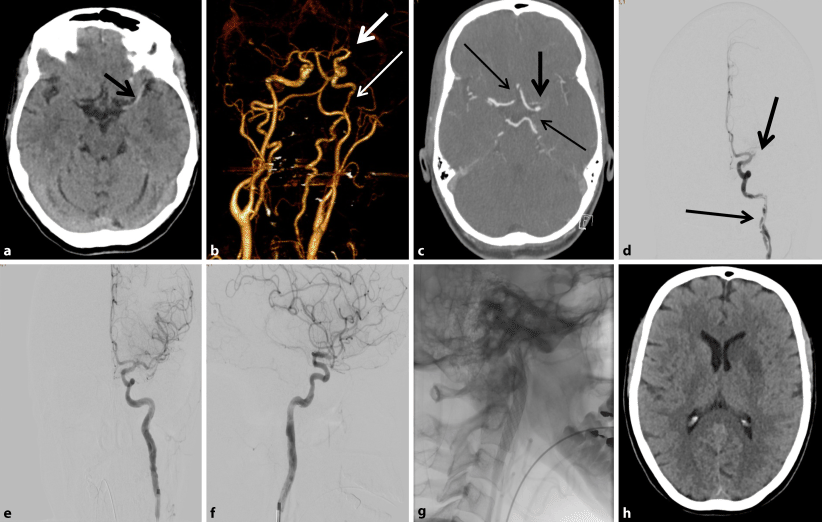

Abb. 3

Kranielle Computertomographie nativ: Dichtes Mediazeichen links (Pfeil) ohne Frühinfarktzeichen im Mediastromgebiet (a). Computerangiographie mit Kontrastmittel: A.-cerebri-media-Verschluss links (Pfeil), Kaliberschwankungen der A. carotis interna links (Pfeil gestrichelt) (b), unzureichende Kollateralisierung über A. communicans anterior und posterior links bei Hypoplasie (Pfeil gepunktet) (c). Katheterangiographie: Verschluss M1-Segment der A. cerebri media links (Pfeil) und Dissektion der A. carotis interna links (Pfeil gepunktet) (d). Nach mechanischer Rekanalisation komplette Wiedereröffnung der A. cerebri media links (TICI 3) (e und f) sowie Stentimplantation der A. carotis interna links (g). Postinterventionelle Computertomographie nativ: ischämischer Stammganglieninfarkt links (h)

Bei Hauptstammverschluss der A. cerebri media links wurde zudem eine Angiographie in Interventionsbereitschaft prozediert. Hier gelang eine komplette Rekanalisierung (TICI 3). Als Ätiologie zeigte sich eine langstreckige Dissektion der linken ACI vom mittleren extrakraniellen Anteil bis in den intrakraniellen Abschnitt reichend. Bei unzureichender intrakranieller Kollateralisierung des vorderen Stromgebiets links und massiven thrombotischen Auflagerungen im Bereich der ACI links erfolgte ein Remodeling der dissezierten ACI mit Hilfe von zwei teleskopartig ineinander positionierten Stents. Periinterventionell wurde ein GPIIb/IIIa-Rezeptor-Antagonist als Bolus intraarteriell und in weiterer Folge über Perfusor verabreicht. Als Sekundärprophylaxe wurde bereits in der Frühphase mit einer dualen Plättchenfunktionshemmung begonnen.

Am Tag nach der Intervention wies die Patientin eine leichtgradige brachiofaziale Hemiparese rechts mit diskreten Wortfindungsstörungen auf (NIHSS 3). Drei Monate nach Ereignis waren keine relevanten Einschränkungen im Alltag zu bemerken (mRS 1).